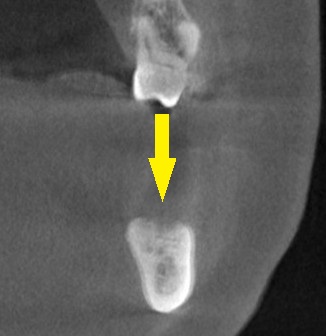

3か月ほどして、CTを撮影してみると、下の写真2段目のように、大きく骨欠損となっていました。

2本のインプラント埋入を目指したいのですが、2本目の部位では、下方に通っている神経までの距離は3~4mm程度でした。